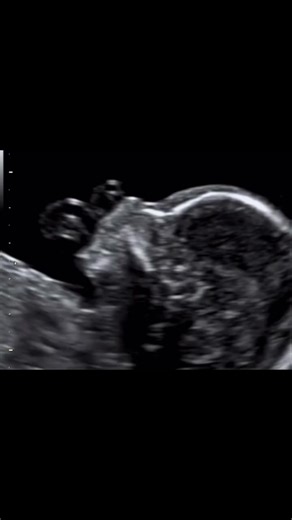

Do you know which ultrasound planes are required to perform a correct exploration of the face? Sagittal and fronto-coronal planes will allow you to see: - Profile: presence of nasal bone, fronto-nasal angle, naso-mental alignment - Orbits: present, symmetrical, correctly positioned, crystalline - Integrity of the lip and nose - Absence of cervical masses Acquire the skills, knowledge and training to recognize, classify and diagnose the majority of the anomalies that we can detect in an ultrasoun